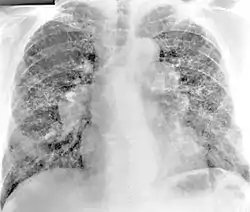

Los hallazgos de la radiografía de tórax de beriliosis son inespecíficos. En las primeras etapas de la enfermedad, los hallazgos radiográficos suelen ser normales. En estadios posteriores se ha informado fibrosis intersticial, irregularidades pleurales, linfadenopatía hiliar y opacidades en vidrio deslustrado . Los hallazgos de la TC tampoco son específicos de la beriliosis. Los hallazgos que son comunes en las tomografías computarizadas de personas con beriliosis incluyen nódulos parenquimatosos en etapas tempranas. Un estudio encontró que las opacidades en vidrio esmerilado se observaron con más frecuencia en la tomografía computarizada en la beriliosis que en la sarcoidosis. En estados posteriores, linfadenopatía hiliar, fibrosis pulmonar intersticial y engrosamiento pleural.